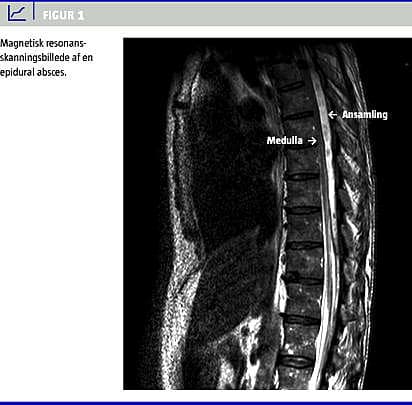

Pga. tiltagende smerter forsøgte man at lægge EPK om til niveau Th 8/Th 9. Proceduren var ukompliceret, men da man kunne aspirere pus fra epiduralrummet, henviste man ham akut til magnetisk resonans (MR)-skanning af medulla spinalis (Figur 1 ) på abscesmistanke. MR-skanningen viste EA, der strakte sig fra Th 3 til Th 12, maks. 8 mm i diameter ud for Th 6 med displacering af medulla.

Tidlig diagnostik og behandling forbedrer udfaldet efter EA. Pga. lav incidens og den ofte langsomtudviklende og atypiske klinik bør man hos alle patienter med EPK og feber eller rygsmerter af ukendt karakter som udgangspunkt have mistanke om EA, også selvom der ikke optræder neurologiske udfaldssymptomer. Den kliniske mistanke kan bestyrkes ved en neurologisk undersøgelse inkl. perkussion af vertebra samt dyrkning fra indstikssted og kateterspids. MR-skanning er den bedste diagnostiske procedure til lokalisering af en eventuel absces.